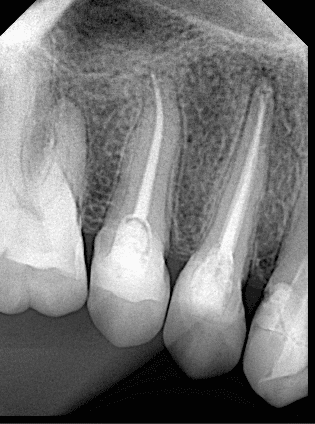

After DME

Cone fitt

After obturation

After preparation

Final x ray